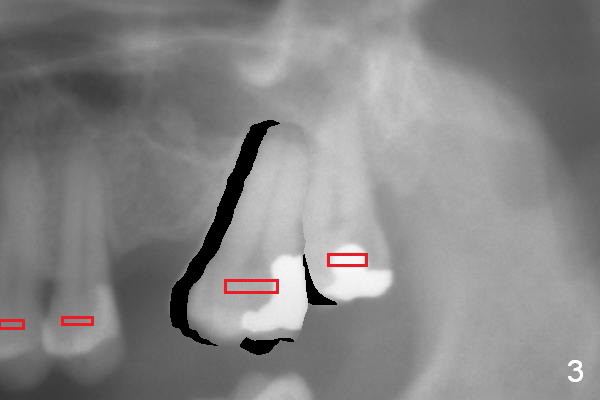

A second option for #14 is segmental orthodontic treatment. Initially keep the tooth #16 and mesial reduction (Fig.2 *). Place brackets between #11 and 16 (Fig.3 red) and open coil spring between #13 and 15.

When the tooth #15 is distalized (Fig.3), place an implant at #14 (Fig.4 green), parallel to the tooth #13 and extract #16 (black). When the implant osteointegrates, place an abutment (Fig.5 pink), provisional (white) and bracket at #14. The implant is used as an anchorage to further distalize #15 until the latter reaches the normal position (Fig.6). CT study shows how much the tooth movement is needed prior to implantation.